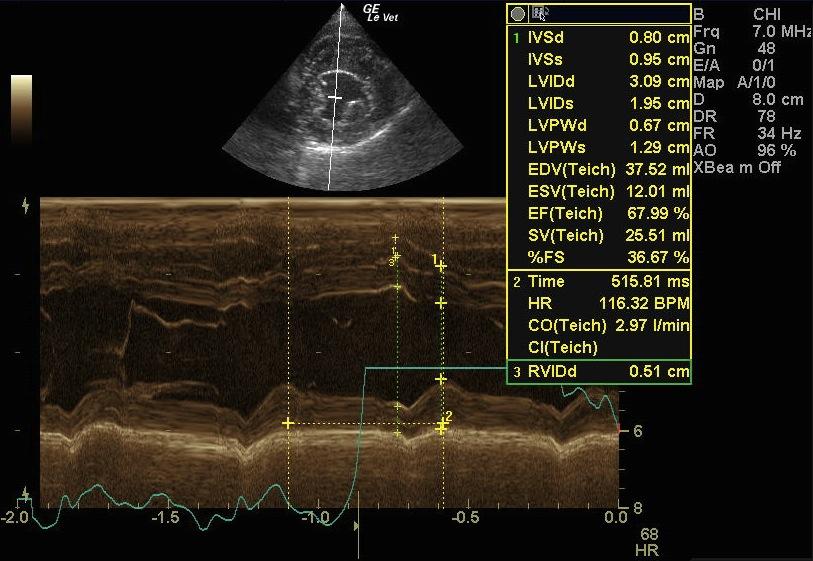

A 9-year-old FS mixed breed dog presented for evaluation of episodic coughing that appeared to be somewhat antibiotic responsive. Survey radiographs showed a normal cardiac silhouette, mild interstitial lung pattern, and an irregular shadow superimposing on the craniobasal cardiac silhouette and adherent to the left thoracic wall from the second to the forth rib. The radiographic changes had been present for almost 2 years.